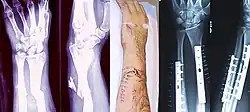

When the initial post-fracture oedema or swelling goes down, the fracture may be placed in a removable brace or orthosis. If being treated with surgery, surgical nails, screws, plates, and wires are used to hold the fractured bone together more directly. Alternatively, fractured bones may be treated by the Ilizarov method, which is a form of an external fixator.

Occasionally, smaller bones, such as phalanges of the toes and fingers, may be treated without the cast, by buddy wrapping them, which serves a similar function to making a cast. A device called a Suzuki frame may be used in cases of deep, complex intra-articular digit fractures.[40] By allowing only limited movement, immobilization helps preserve anatomical alignment while enabling callus formation, toward the target of achieving union.

Splinting results in the same outcome as casting in children who have a distal radius fracture with little shifting.[41]